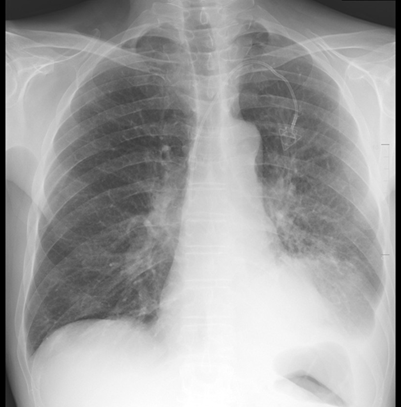

Upon discharge, he was educated on the importance of taking

his medications for copd, specifically his albuterol and ipratropium

nebulizers. Four days after discharge from our facility, he received a

single-lumen power port vascular catheter through the left subclavian vein for

chemotherapy. An outpatient cxr showed mild pulmonary venous congestion without

overt edema with a stable, large, mass-like opacity in the left lower lobe. Our

patient was given close follow up with hematology-oncology, pulmonology, and

primary care to optimize his management for stage iva nsclc.